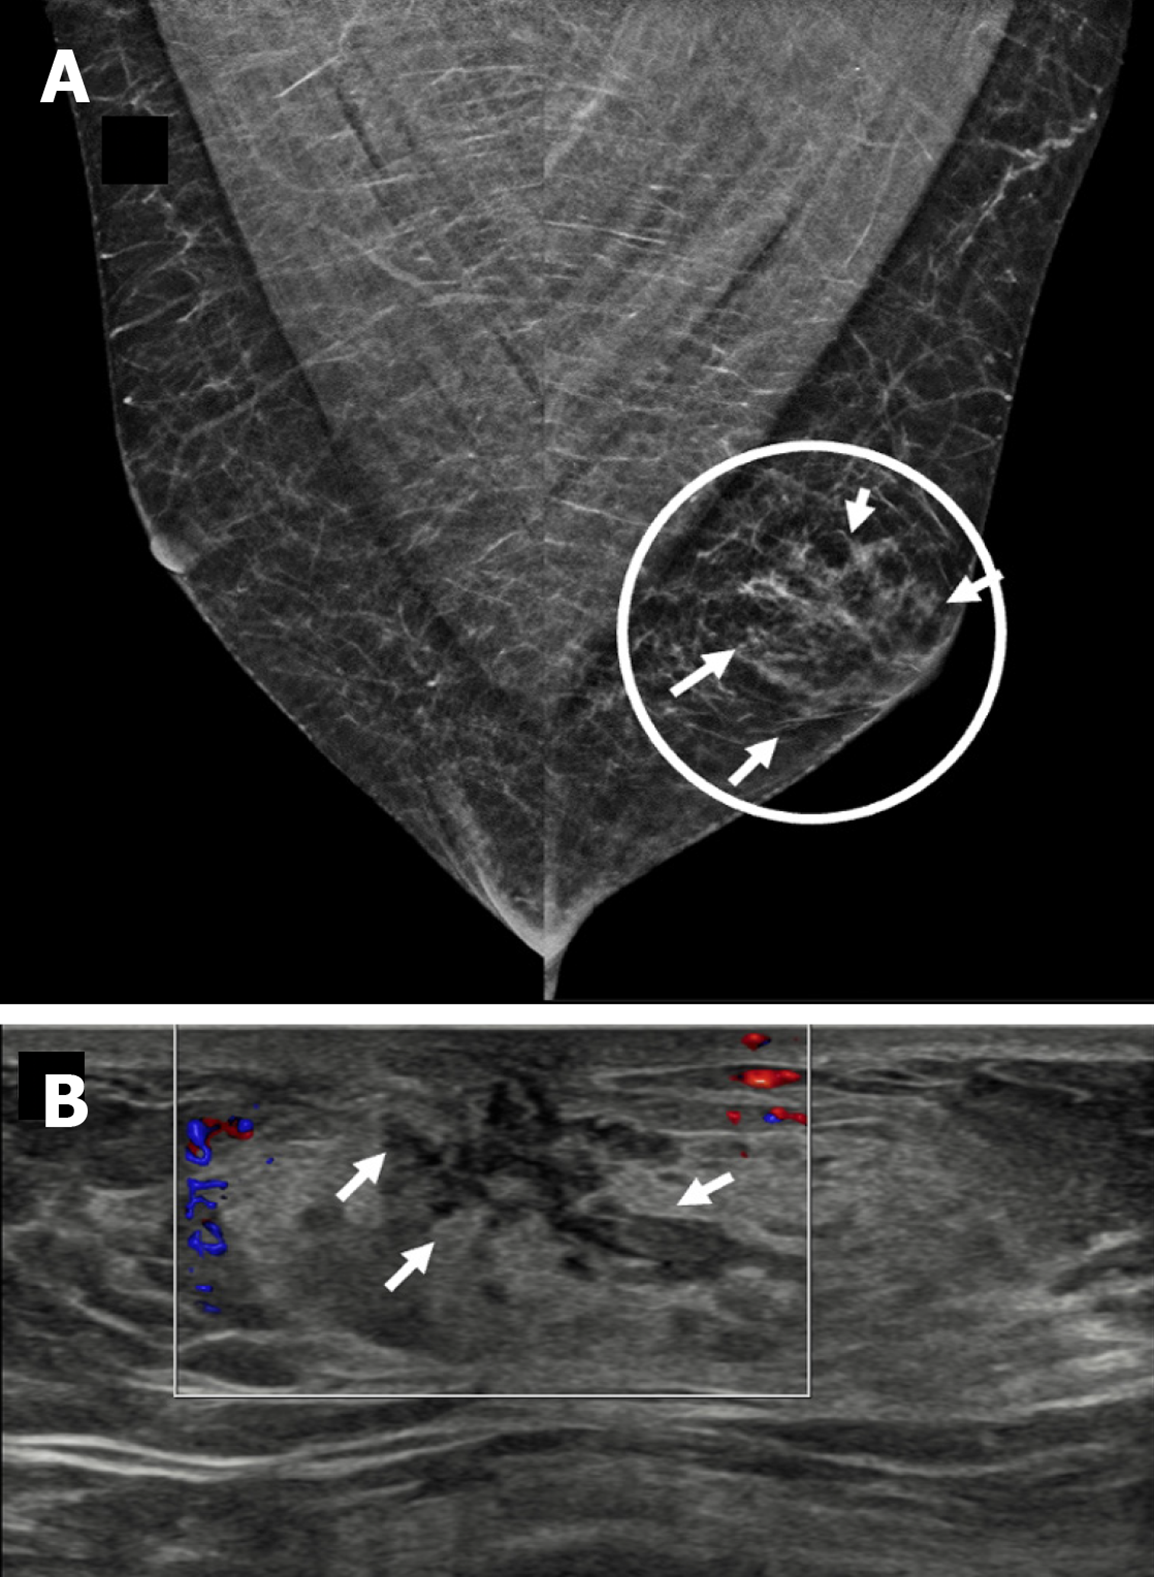

Figure 5 Dendritic gynecomastia in a 69-year-old male with a tender soft mass in the left breast.

A: Mediolateral oblique mammography view showing a triangular flame-shaped area of increased density in the retroareolar location of the left breast (encircled); B: Ultrasound image showing an irregular hypoechoic retroareolar lesion with dendritic projections inside the underlying glandular fat (small white arrows).